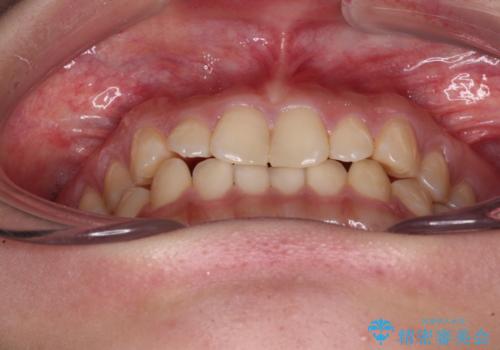

治療途中の奥歯と矯正治療の後戻り インビザライン・ライトによる矯正治療

- 20代女性

- インビザライン・ライト

- 根管治療を行ったままの奥歯と、矯正治療の後戻りを気にして来院された患者様です。

根管治療された歯に症状はなく、オールセラミッククラウンにて補綴治療を行うこととしました。

矯正治療の後戻りは軽微であったため、インビザラインの簡易パッケージであるインビザライン・ライトを用いて歯列を整えることとしました。

クラウンはよりよい咬み合わせで装着したいため、インビザラインを1セット使用して概ね歯列を整えた時点で補綴治療を行い、その後仕上げの矯正治療を行いました。